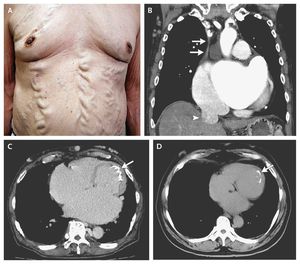

physical examination revealed varices of the chest and abdominal wall (image a)which may be caused by collateral circulation associated with obstruction of the superior vena cava (SVC). Chest (ct) showed SVC obstruction and dilatation of the inferior vena cava (image b) Endocardial calcification is obviously seen on image c so it is a svc obstruction...

The observed varices of the abdominal region is called “Caput Medusae”.

There are varices of the chest and abdominal wall caused by collateral circulation associated with obstruction of the superior vena cava. Paraumbilical and abdominal-wall varices can complicate cirrhosis but do not typically extend to the chest wall.